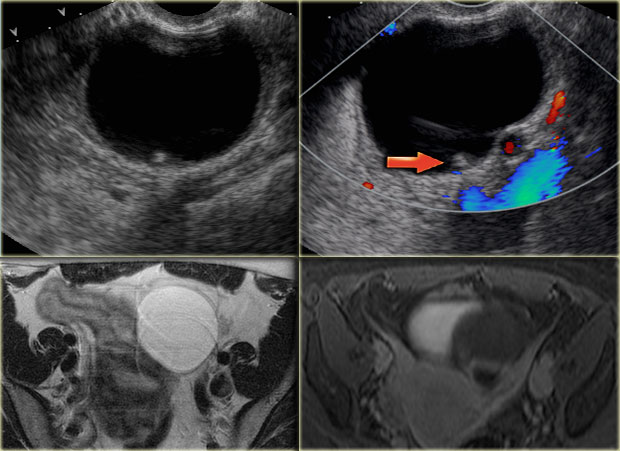

The ultrasound images show multiple simple and one complex right ovarian lesion (red arrow).

The latter demonstrates diffuse low-level echos and no flow on Doppler.

Note that there is a good through transmission (blue arrow).

These findings indicate the presence of a hemorrhagic cyst.

Continue with the MR-images.

Hemorrhagic ovarian cyst Hemorrhagic ovarian cyst

Axial and sagittal T2W images from the same patient.

The right ovary contains multiple simple T2 bright cysts with thin borders and no solid components.

On the axial image there is one lesion, that is dark on T2, i.e. a complex cyst (arrow).

There is a small amount of ascites around the right ovary, but not enough to raise concern of a possible neoplasm.

On the T1-weighted image without fatsat the complex cyst is bright, indicating either fat or blood content.

On the T1-weighted image with fatsat the lesion remains bright, ruling out a fatty lesion.

After the administration of Gd there is no enhancement, confirming that this is a hemorrhagic ovarian cyst.

An endometrioma would be in your differential.

Note that subtraction images are best to demonstrate the lack of enhancement in a lesion, that is bright on the pre-contrast T1-weighted image.